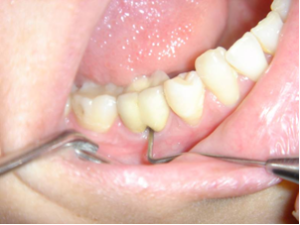

Nettoyage inter-radiculaire.

Reprise du traitement endodontique , séparation des racines et curetage inter-radiculaire.

Une espace entre les deux racines est laissé accessible pour le passage d'une brossette inter-dentaire.

Une espace entre les deux racines est laissé accessible pour le passage d’une brossette inter-dentaire.